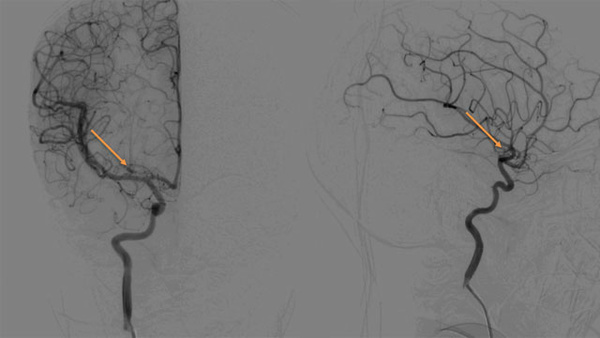

From Invisible to Curable Endovascular Cure of a Heubner’s Micro-AVM in a Child